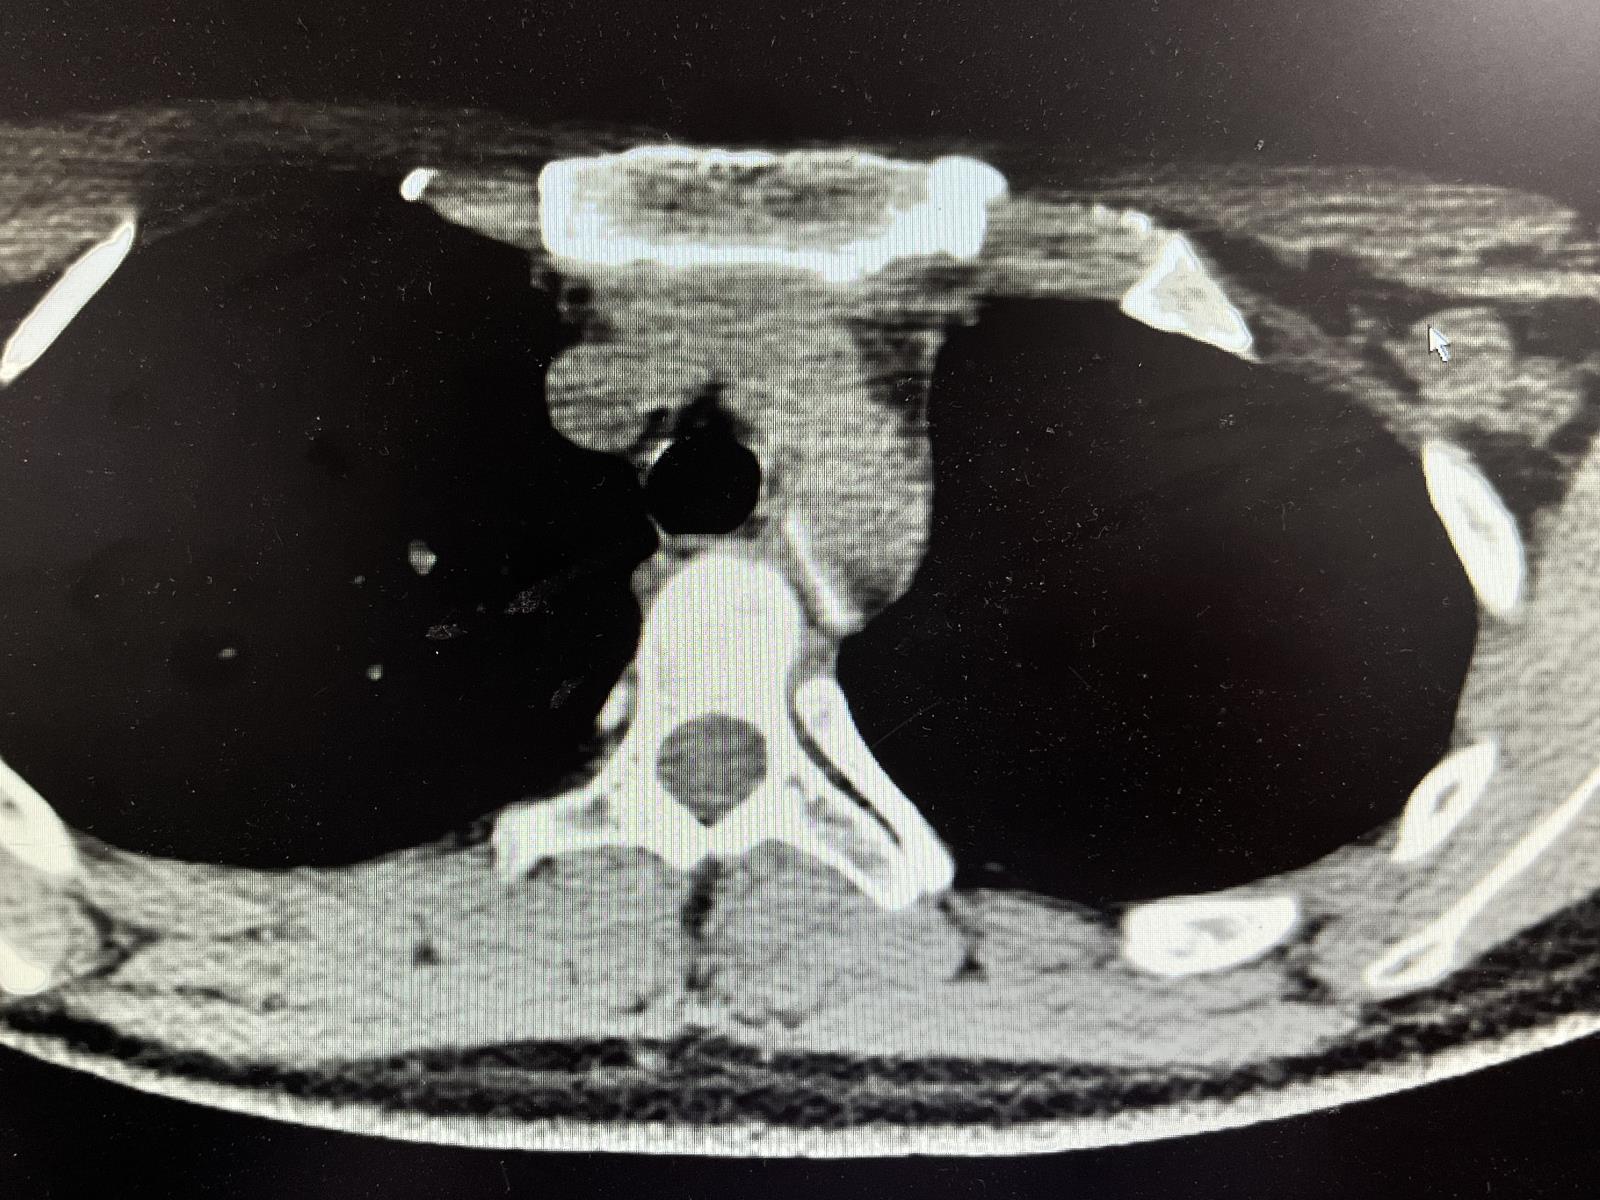

近日,绵阳市第三人民医院消化内科住院总邓倩曦接到急诊科电话通知,有病人吃饭时误将鸭骨头卡在食管,经CT检查显示鸭骨头较大且位置很深,请消化内科会诊共同协商治疗方案。经会诊,消化内科邓倩曦表示患者需要立即进行急诊食管镜将异物取出,避免鸭骨头继续下降造成食管穿孔影响患者生命安全。

(图:鸭骨头较大且位置很深)